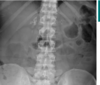

This abdominal X-ray shows multiple loops of dilated bowel with a loss of bowel markings **indicating large bowel obstruction. **